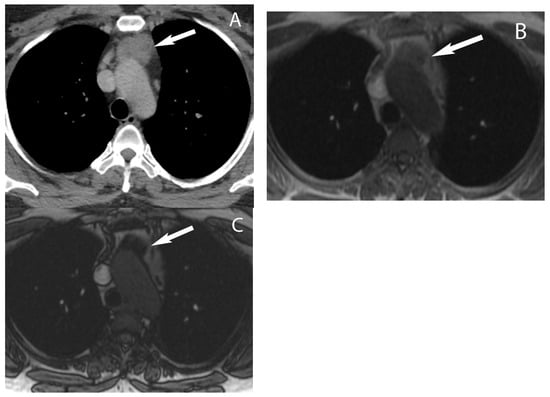

Visceral (Middle) Compartment

8. Cystic Lesions

9. Hypervascular Lesions

10. Esophageal Lesions